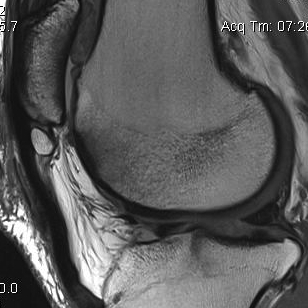

MRI

Cyst / Degeneration

Traction spurs / calcification / ossicles